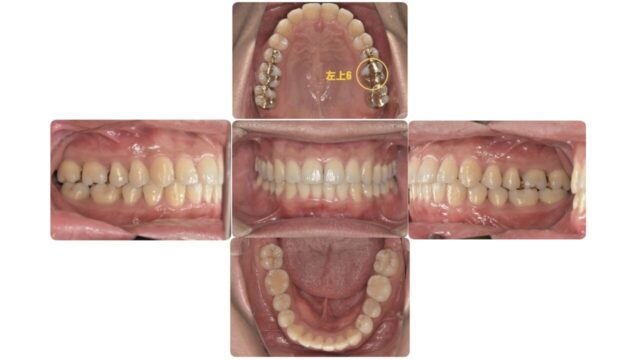

まずはレントゲン写真と口腔内写真をご覧下さい

今回の部位は左上6番です

拡大して見てみましょう。

所々色が暗くなってるところはカリエスになっているところです。